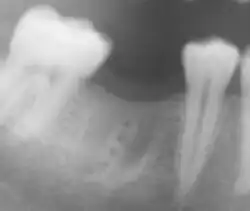

Komplikationen

Im Vordergrund der Komplikationen stehen alle Faktoren, die eine Infektion im Implantationsbereich begünstigen. Zahnimplantate unterliegen der Gefahr einer Periimplantitis, einer Entzündung des Knochengewebes um das Zahnimplantat herum. Die Verbindung zwischen Implantat und Knochen ist nahezu ausschließlich durch bakterielle Einflüsse zerstörbar (Auflösung der Knochenmatrix durch Matrix-Metalloproteasen, MMPs). Die Ursache ist entweder auf Operationsfehler oder auf eine ungenügende Mundhygiene des Patienten zurückzuführen. Die Periimplantitis führt zu einem Knochenabbau, der letztendlich den Ausfall des Implantats bewirkt. Eine Zahnimplantation wird als Misserfolg gewertet, wenn das Implantat mobil ist oder einen periimplantären Gewebsschwund von mehr als 1 mm im ersten Jahr aufweist. Eine Periimplantitis kann durch prophylaktische Maßnahmen zusammen mit einer Antibiotikatherapie behandelt werden. Eine Periimplantitis ist auf einer Röntgenaufnahme zu erkennen.

Bei zusammengesetzten Implantaten befinden sich zwischen dem eigentlichen Implantat und dem Aufbau (Abutment) Spalten und Hohlräume, in die Keime aus der Mundhöhle eindringen können. Später gelangen diese Keime wieder in das angrenzende Gewebe und können so eine Periimplantitis verursachen. Als Prophylaxe sollten diese Implantatinnenräume versiegelt werden.[73]